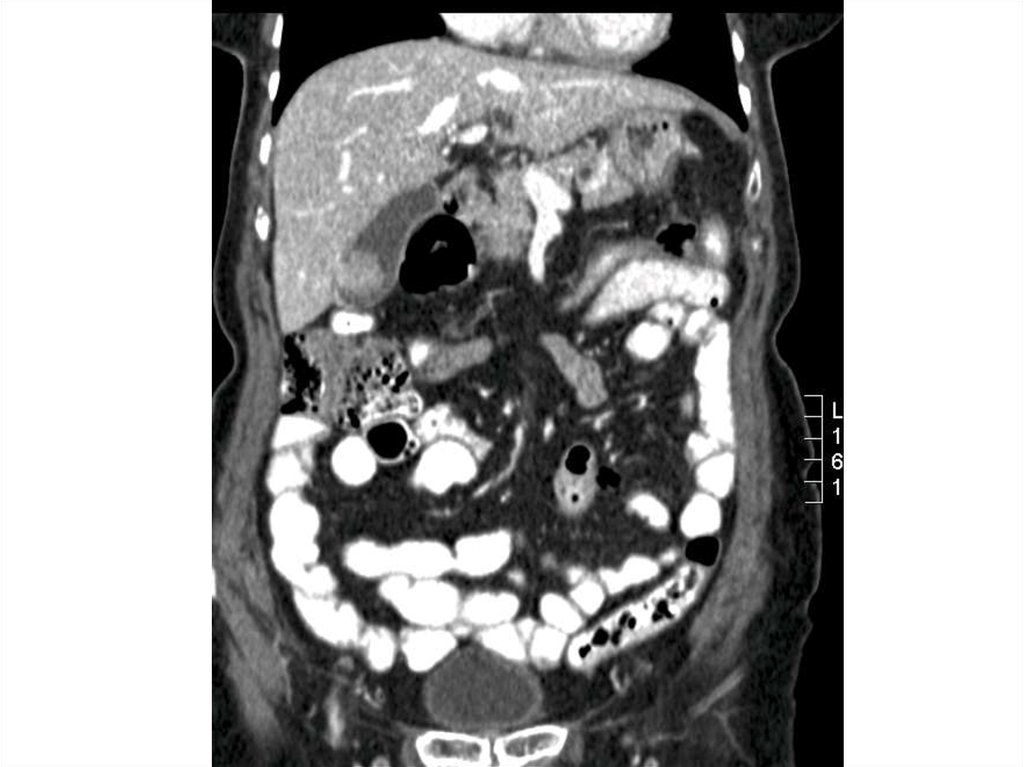

Специальные исследования

Эмфизематозный холецистит